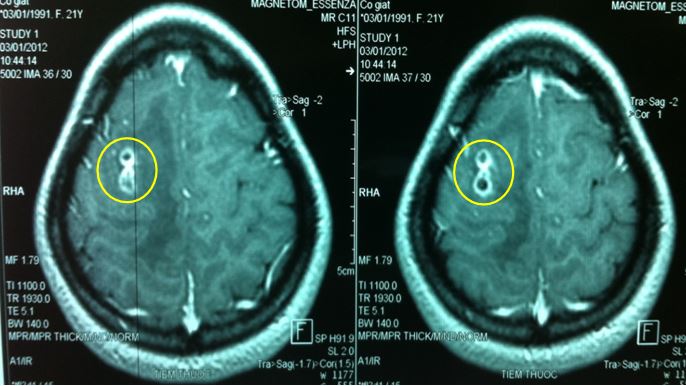

Hình ảnh MRI : tổn thương tại thùy đỉnh phải, ngấm thuốc dạng viền và có phù não xung quanh.

Kết luận của chẩn đoán hình ảnh: theo dõi tổn thương do Toxoplasma.